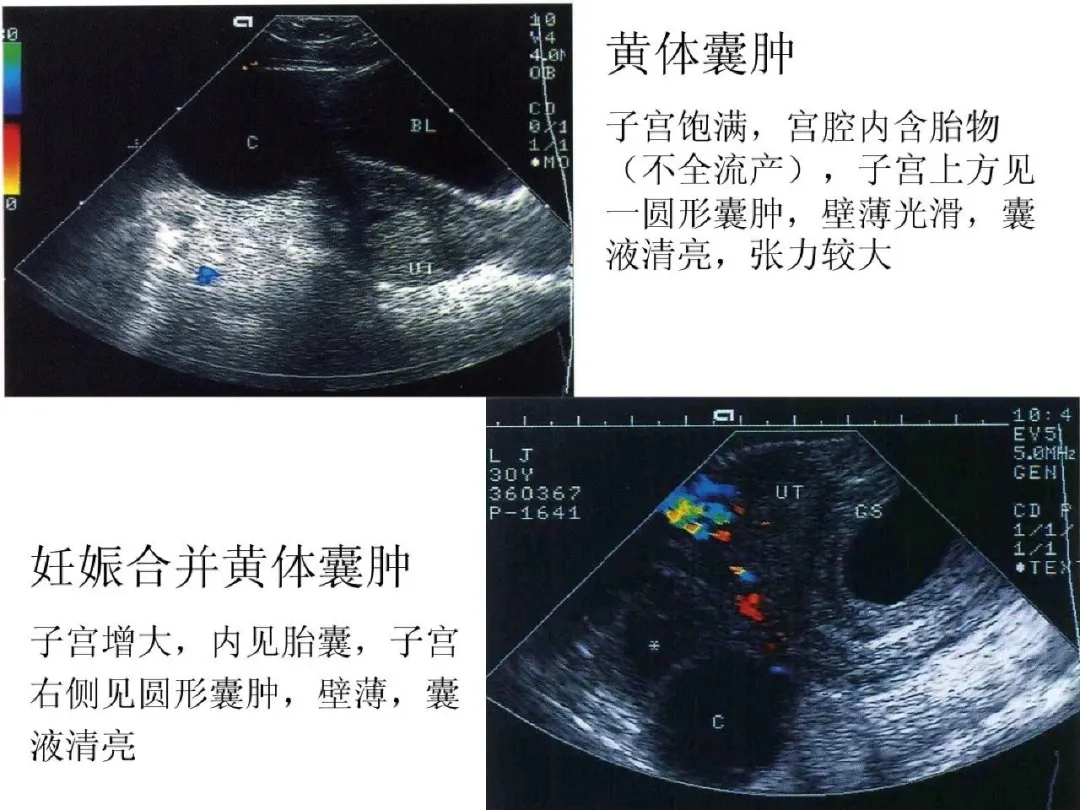

●黄体囊肿(多见于子宫内膜分泌期或妊娠早期):大小多为2-3cm或更大;个别黄体囊肿可破裂出血而出现急腹症。